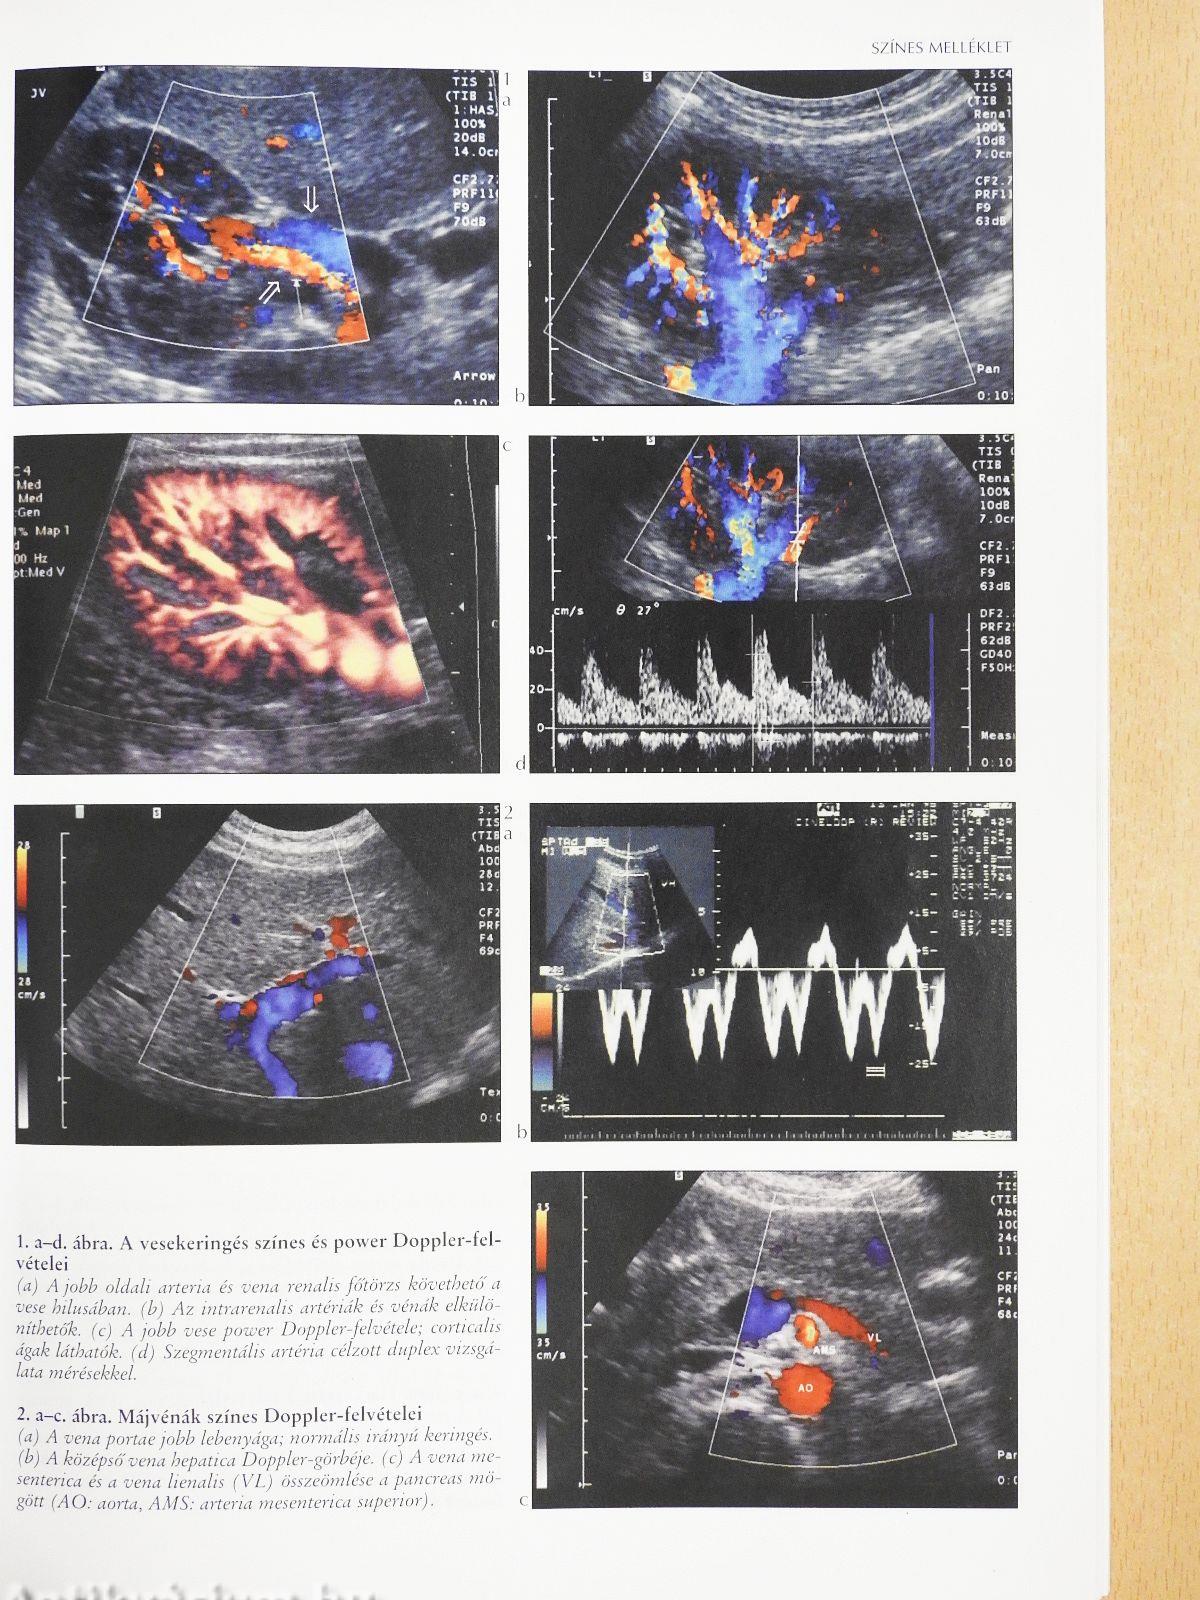

A vesekeringés duplex ultrahangvizsgálata60

Komplex hasi ultrahangvizsgálat42